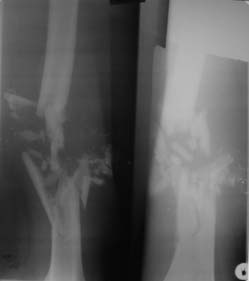

ОГНЕСТРЕЛЬНОЕ (ПУЛЕВОЕ) СКВОЗНОЕ РАНЕНИЕ СРЕДНЕЙ ТРЕТИ ПРАВОГО БЕДРА. ОГНЕСТРЕЛЬНЫЙ ОСКОЛЬЧАТЫЙ ПЕРЕЛОМ ПРАВОЙ БЕДРЕННОЙ КОСТИ В СРЕДНЕЙ ТРЕТИ С ПОВРЕЖДЕНИЕМ МАГИСТРАЛЬНЫХ НЕРВНЫХ СТВОЛОВ ПРАВОЙ НИЖНЕЙ КОНЕЧНОСТИ (31.10.2011г.). ПОСТГЕМОРРАГИЧЕСКАЯ АНЕМИЯ.

На рентгенограмме правой бедренной кости 02.11.2011г. определяется оскольчатый перелом средней трети ее. В мягких тканях множественные мелкие инородные тела металлической плотности менее 1-го миллиметра в диаметре – «металлическая пыль».

На рентгенограмме правой бедренной кости определяется оскольчатый перелом средней трети ее без значительного смещения отломков. В мягких тканях множественные мелкие инородные тела металлической плотности менее 1-го миллиметра в диаметре – «металлическая пыль» (снимки переданы в в/ч 26826).